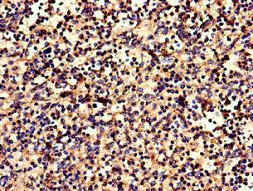

CSB-PA005679LA01HU

Immunohistochemistry of paraffin-embedded human spleen tissue using CSB-PA005679LA01HU at dilution of 1:100